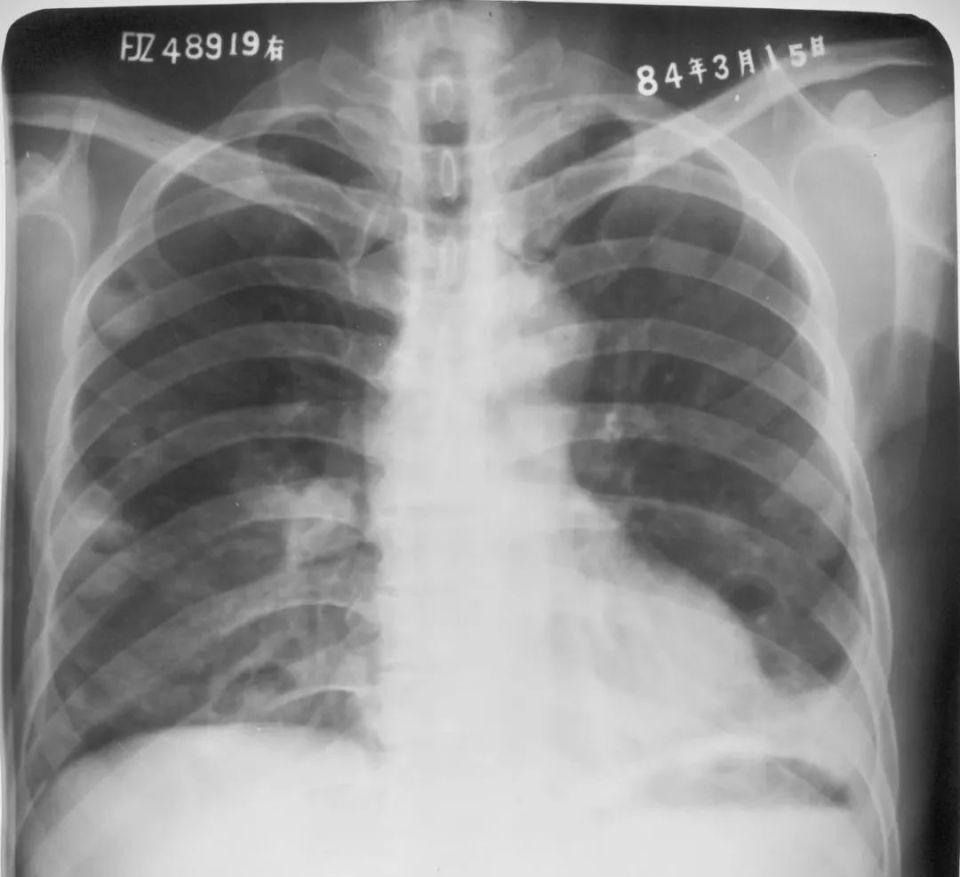

婴幼儿肺炎

胸部正位片示:两肺内带及左肺下野可见不规则的小片状或斑片状边缘模糊的致密阴影,阴影密度不均,局部可见支气管充气征